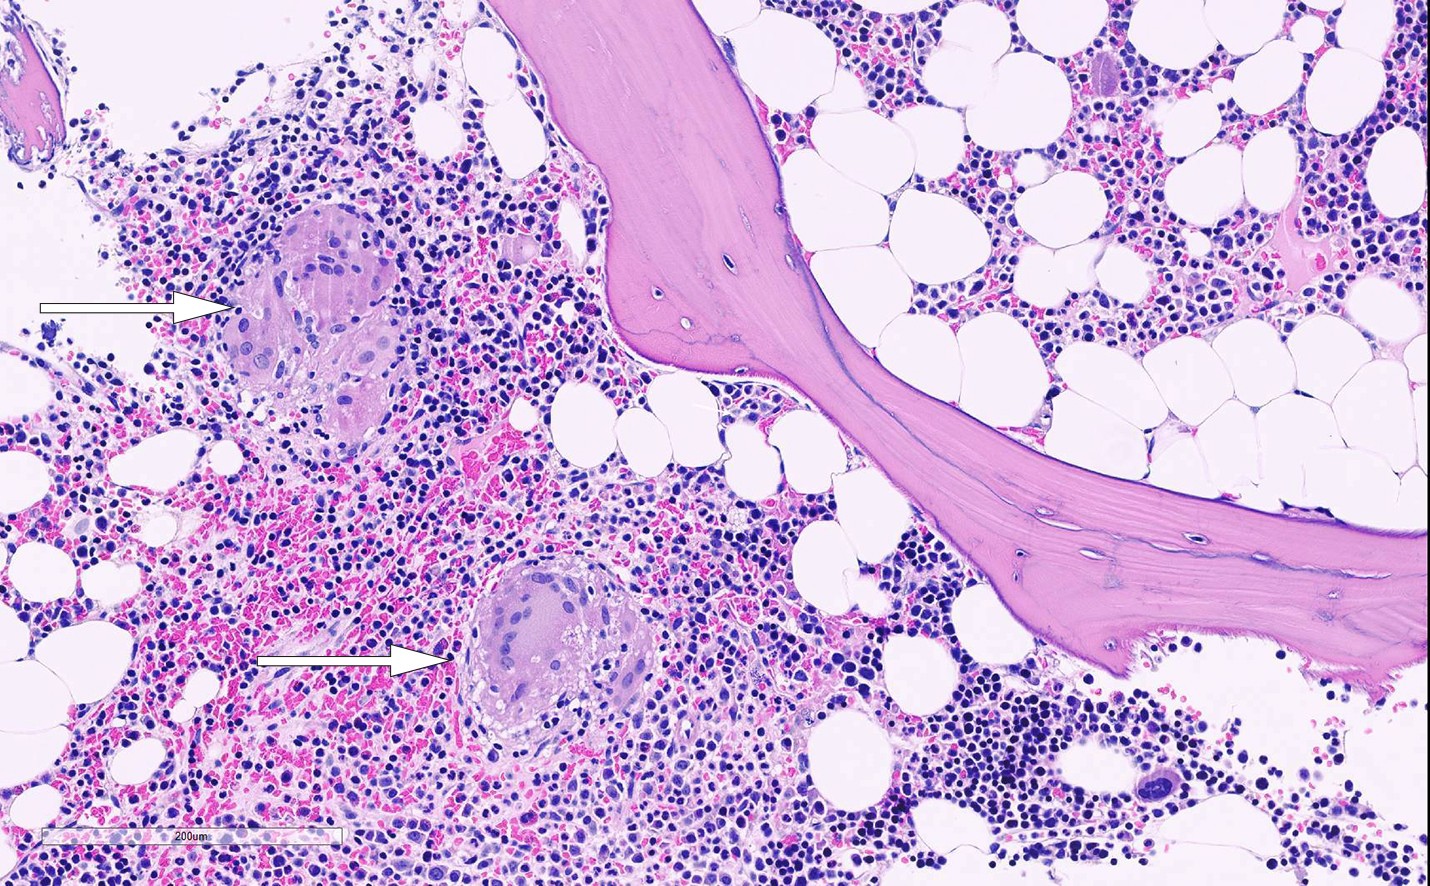

Funn på MR reiste primært mistanke om hematologisk eller metastatisk sykdom. Det ble derfor utført beinmargsaspirat og -biopsi. Aspirasjon av beinmarg viste en lett cellefattig marg med få megakaryocytter, men god modning i myelopoese på 62 % (25–62 %) og erytropoese på 21 % (10–35 %), og det var ingen umodne celler eller plasmacelleekspansjon. Samlet tydet dette på god beinmargsfunksjon, uten holdepunkt for primær hematologisk sykdom eller infiltrasjon av beinmargsfremmede celler som kunne reise mistanke om malign sykdom eller skjelettmetastaser. Etter en uke forelå svar fra beinmargsbiopsien, som viste en lett cellefattig beinmarg med hematopoetiske celler i om lag 30–40 % av snittflaten. Spredt i margrommene var det flere velavgrensete ansamlinger av celler med rikelig eosinofilt cytoplasma og avlange, svakt bøyde kjerner forenlig med epiteloide histiocytter i granulomer. Det var også innslag av noen flerkjernede kjempeceller (figur 2). Det ble ikke påvist fremmedlegememateriale eller nekrose i granulomene. Immunhistokjemisk undersøkelse med antistoff mot T-cellemarkør CD3 viste noe økt forekomst av T-lymfocytter spredt i margrommene, med fortetning rundt granulomene. Dette ble oppfattet som reaktivt. Det var vanlig mengde plasmaceller i beinmargen, og disse viste vanlig bitypisk fordeling ved farging for lette kjeder (kappa og lambda), forenlig med polyklonale plasmaceller. Polymerasekjedereaksjonstest (PCR) for mykobakterier, inkludert Mycobacterium tuberculosis, var negativ.

Det forelå altså en beinmarg med flere epiteloidcellegranulomer uten nekrose, hvilket kan ses ved sarkoidose. Funnet ble vurdert å være forenlig med sarkoidose i beinmarg (ramme 1).

Den aktuelle pasienten hadde ryggsmerter av ny og annen karakter enn hun tidligere hadde hatt, uten bedring av konservativ behandling. Det ble funnet indikasjon for bildediagnostikk for å utelukke underliggende sykdom. MR avbilder beinmargens bløtdelskomponent direkte og er sensitiv for påvisning av patologiske prosesser i skjelettet (5). Infiltrasjon i beinmarg ved MR er et lite spesifikt funn som ses ved flere tilstander i skjelettet (4). Et histologisk bilde med ikke-nekrotiserende granulomer, som hos vår pasient, kan forekomme ved sarkoidose, malignitet og infeksjoner (10). Diagnosen sarkoidose sikres ved biopsi (11), og det er foreslått kliniske diagnosekriterier for sarkoidose ramme 1) ((11).